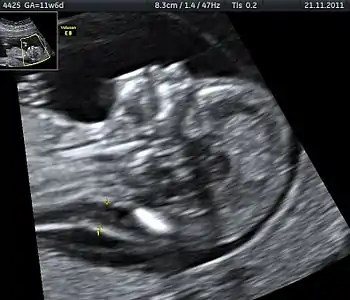

Nuchal scan (NT procedure) is performed between 11 and 14 weeks of gestation, because the accuracy is best in this period. The scan is obtained with the fetus in sagittal section and a neutral position of the fetal head (neither hyperflexed nor extended, either of which can influence the nuchal translucency thickness). The fetal image is enlarged to fill 75% of the screen, and the maximum thickness is measured, from leading edge to leading edge. It is important to distinguish the nuchal lucency from the underlying amniotic membrane.[8]

Normal thickness depends on the crown-rump length (CRL) of the fetus. Among those fetuses whose nuchal translucency exceeds the normal values, there is a relatively high risk of significant abnormality.